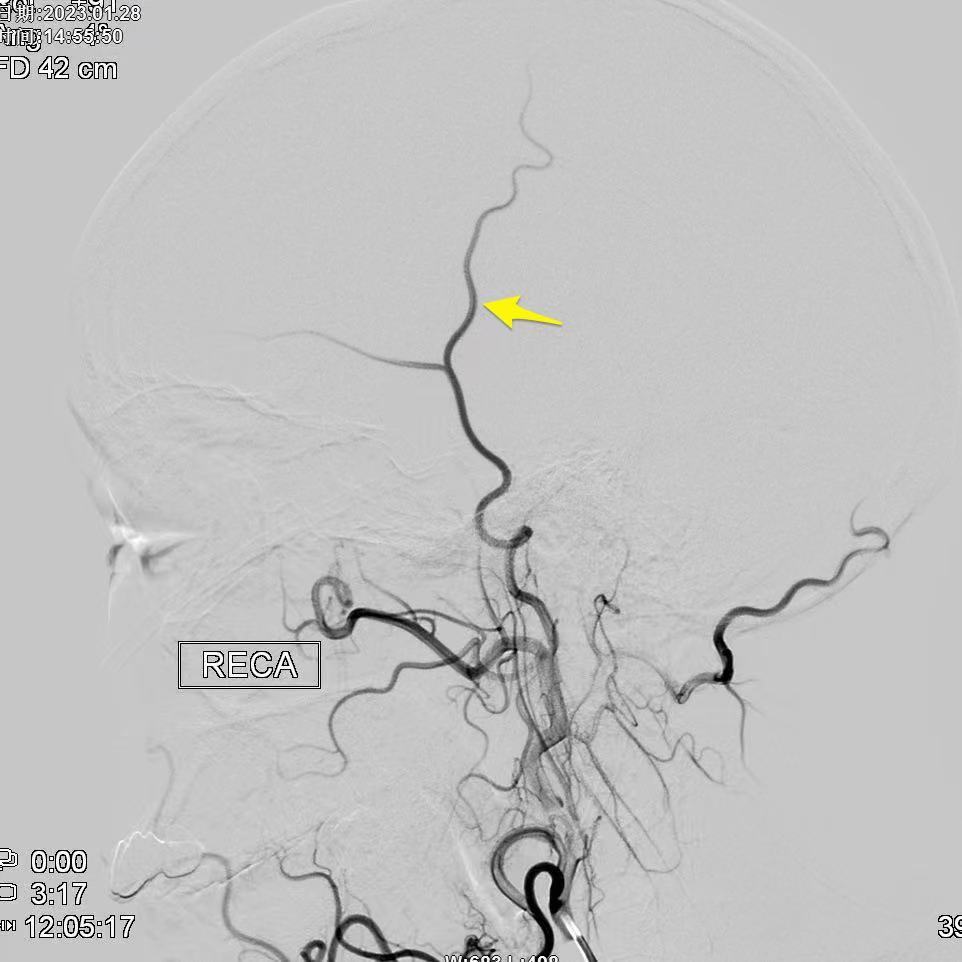

昆明三博2023:颞浅动脉一大脑中动脉M3吻合术